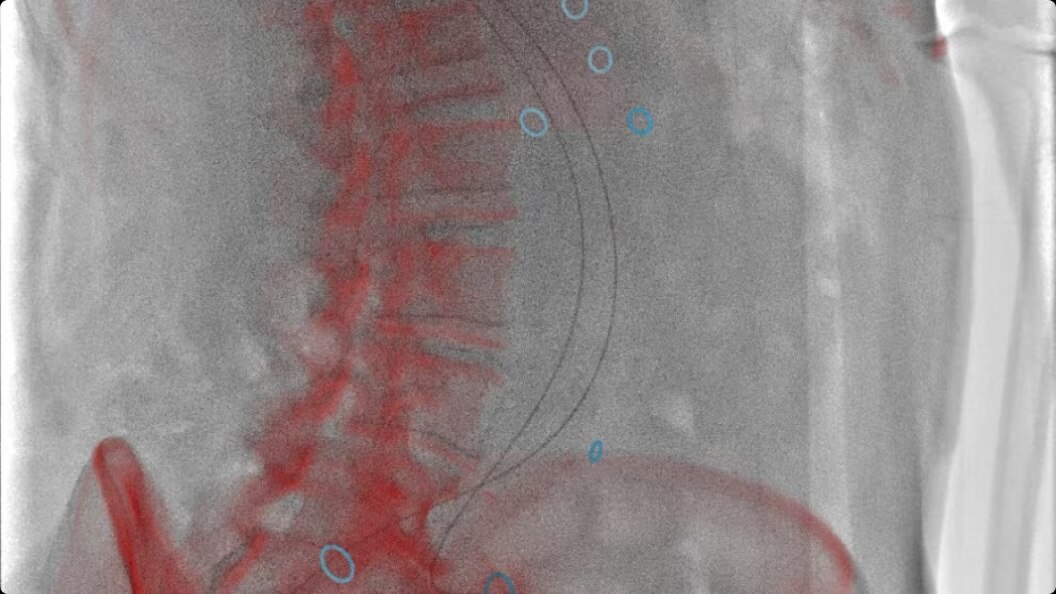

Enhance your clinical capabilities

Enable flexible cone-beam computed tomography (CBCT) even on obese patients and adapt to constantly evolving procedures and techniques.